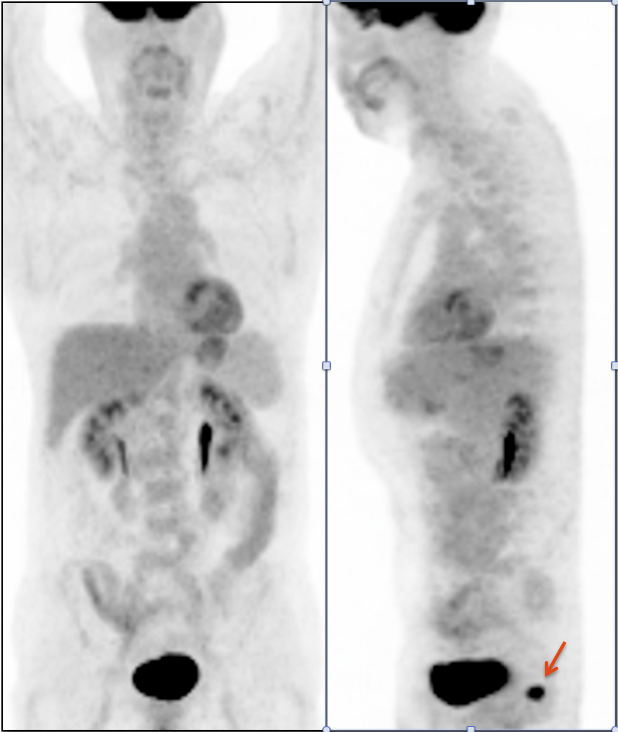

• Beware the small rectal cancer!  As the ano-rectal region frequently demonstrates intense physiologic uptake, it is very easy to overlook a rectal malignancy, especially if it is an incidental finding.  To avoid this error, always evaluate the rectum carefully on the sagittal whole body images.  It is shocking to see how readily apparent a rectal cancer can be on these images, yet so easily overlooked in the axial plane.